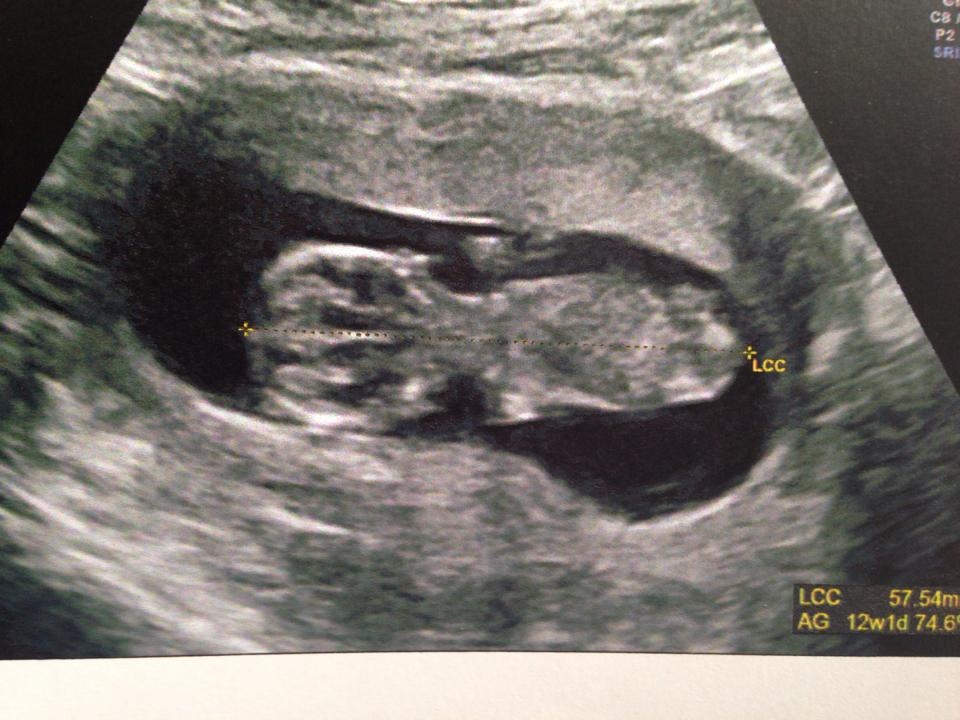

alors voila ma crevette qui fait 57 mm bébé est de dos il ne s'est pas laissé voir du coup je connaitrait le sexe a la prochaine echo ...... le 1er avril mouahahha

• bb2.jpg

bb2.jpg

129.8 KB · Affichages: 61